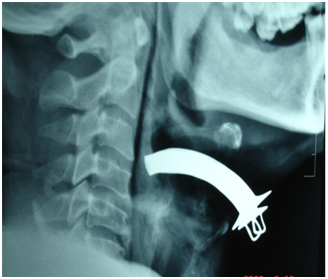

Figure 1 X ray soft tissue neck lateral view revealed a defect in the thyrohyoid membrane.

Figure 2 Lower end of the tube abutting the posterior pharyngeal wall.